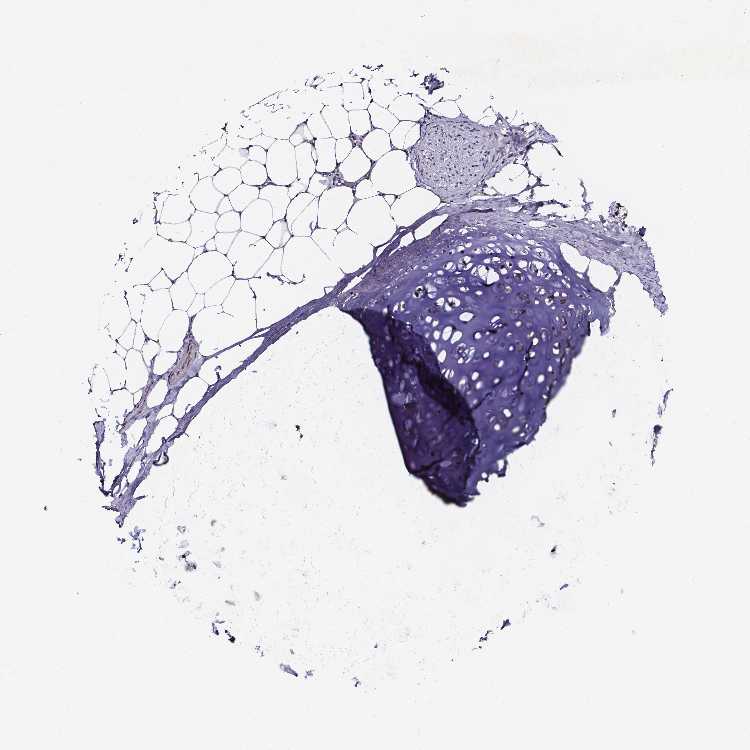

SOFT TISSUE 1 - Antibody stainingi

Antibody staining in the annotated cell types in the current human tissue is reported as not detected, low, medium, or high, based on conventional immunohistochemistry profiling in selected tissues. This score is based on the combination of the staining intensity and fraction of stained cells.

Each image is clickable and will lead to virtual microscopy that enables deeper exploration of all samples and also displays staining intensity scores, fraction scores and subcellular localization as well as patient and tissue information for each sample.

Antibody HPA064621

Chondrocytes Not detected

Fibroblasts Not detected

Peripheral nerve Not detected